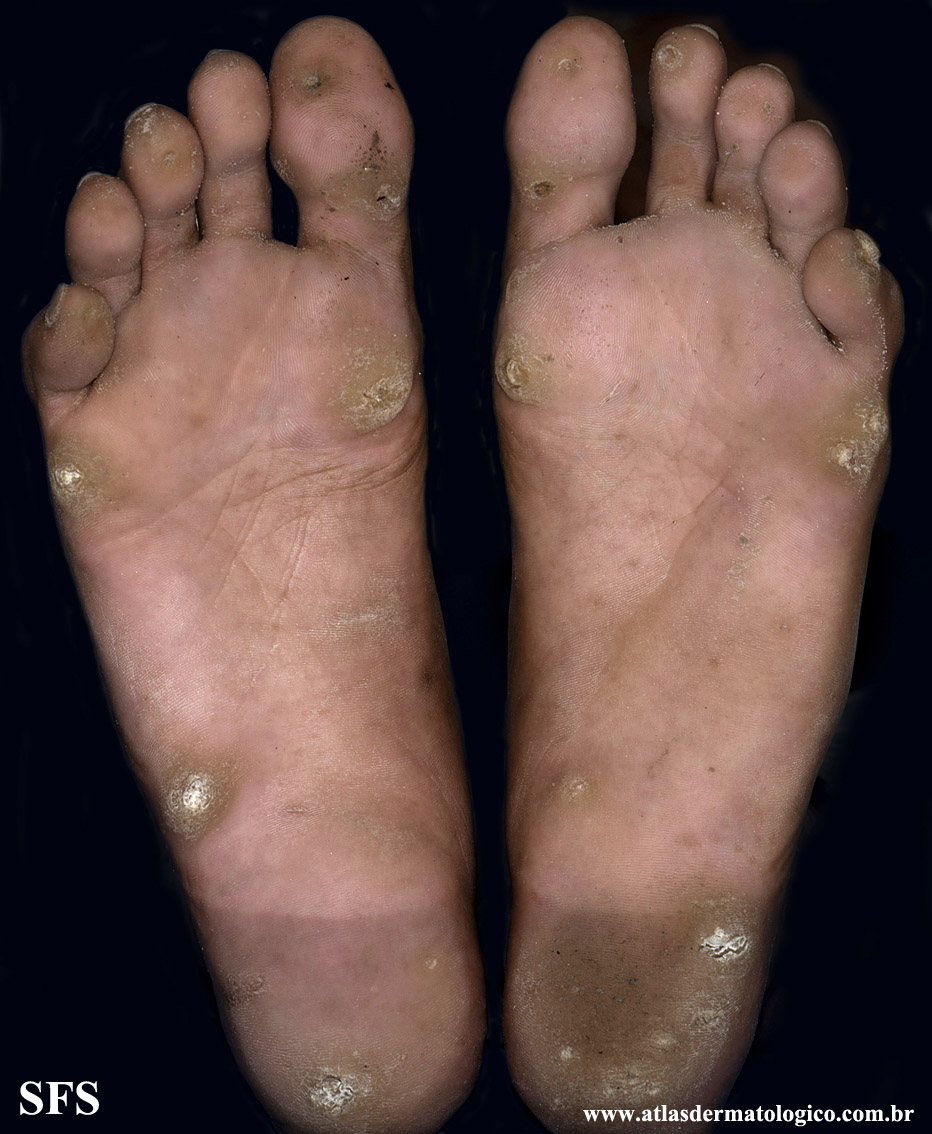

palmoplantar_keratoderma-focal_keratoderma